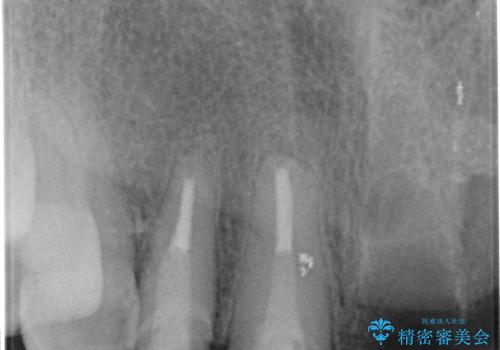

一見して問題ないように見える左側の2前歯は、セラミックを除去してみると亀裂や虫歯の再発が見られました。

抜歯時に可及的に歯肉のボリュームを保つよう骨充填材とコラーゲン製剤による填塞を行い審美的かつ機能的なブリッジとなるよう治療を進めます。